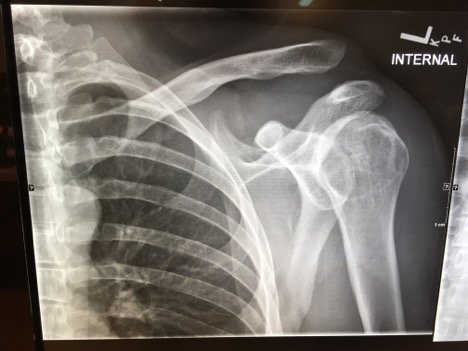

Plain films of the left shoulder showed elevation of the left clavicle above the acromion. There was an increase in the acromioclavicular (AC) and coracoclavicular (CC) distances (increased joint distances marked with red and blue arrows, respectively). A normal AC joint measures 1-3 mm whereas a normal CC distance measures 11-13 mm.1 The injury was classified as a Rockwood type III AC joint separation.

Initial evaluation with imaging includes plain films with three views: the anterior-posterior (AP) view with the shoulder in internal and external rotation as well as an axillary, or scapula-Y view (sensitivity 40%, specificity 90% for all films).6,7 AC joint injuries are classified by the Rockwood system.8 Type I involves a sprain or incomplete tear of the AC ligaments with an intact CC ligament. The AC joint appears normal on X-ray, but can become widened with stress, achieved by having the patient hold a 10-15 pound weight from each forearm.1,9 Type II injuries involve a torn AC ligament, disrupting the AC joint. The AC joint appears widened on radiographs.1,9 The AC and CC ligaments are disrupted in type III injuries with an increased CC distance of 25%-100% on plain films.1,10 In addition to torn AC and CC ligaments, the clavicle is posteriorly displaced in a type IV injury. Because the AP film may not reveal the posterior displacement of the clavicle, the axillary view is vital for correct classification of type IV injuries.1 A type V injury involves disruption of the AC and CC ligaments as well as torn muscle attachments of the trapezius and deltoid on the clavicle and scapula, leading to greater AC joint displacement on radiographs. The CC distance appears 100%-300% greater than normal.1,10 Type VI injuries are caused by a direct blow to the superior surface of the clavicle resulting in inferior displacement. On X-ray, the lateral end of the clavicle is inferior to the acromion and coracoid processes in Type VI injuries.1